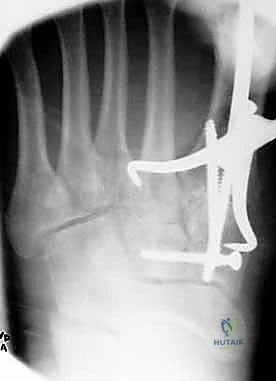

1. الرد المفتوح والتثبيت الداخلي (ORIF - Open Reduction and Internal Fixation)

هذا هو الإجراء الكلاسيكي والأكثر شيوعاً. يهدف إلى إعادة العظام إلى مكانها الطبيعي (الرد) وتثبيتها باستخدام معدات طبية (مسامير، شرائح، أو أسلاك) حتى تلتئم الأربطة والعظام.

خطوات العملية:

1. التخدير: يتم إجراء الجراحة تحت التخدير الموضعي (النصفي) أو العام.

2. الشق الجراحي: يقوم الدكتور هطيف بعمل شق جراحي دقيق (أو شقين) على ظهر القدم للوصول إلى المفاصل المصابة، مع الحرص الشديد على حماية الأعصاب والأوعية الدموية الدقيقة في تلك المنطقة باستخدام مبادئ الجراحة المجهرية.

3. التنظيف والرد: يتم تنظيف المفاصل من أي شظايا عظمية أو أنسجة محشورة تمنع عودة العظام لمكانها. ثم يتم إعادة العظام بحذر شديد إلى محاذاتها التشريحية الدقيقة (القوس الروماني).

4. التثبيت (Fixation): يتم تثبيت العظام باستخدام مسامير معدنية خاصة (Solid or Cannulated Screws) تعبر المفاصل لتثبيتها بإحكام. في بعض الحالات، يتم استخدام شرائح معدنية صغيرة للحفاظ على الاستقرار.

5. مسمار ليزفرانك: الخطوة الأهم هي وضع "مسمار ليزفرانك" (Lisfranc Screw) الذي يمر من العظم المسماري الإنسي إلى قاعدة المشط الثاني، لتعويض وظيفة الرباط الممزق.

6. الإغلاق: يتم إغلاق الشقوق الجراحية بعناية تجميلية ووضع القدم في جبيرة لحمايتها.